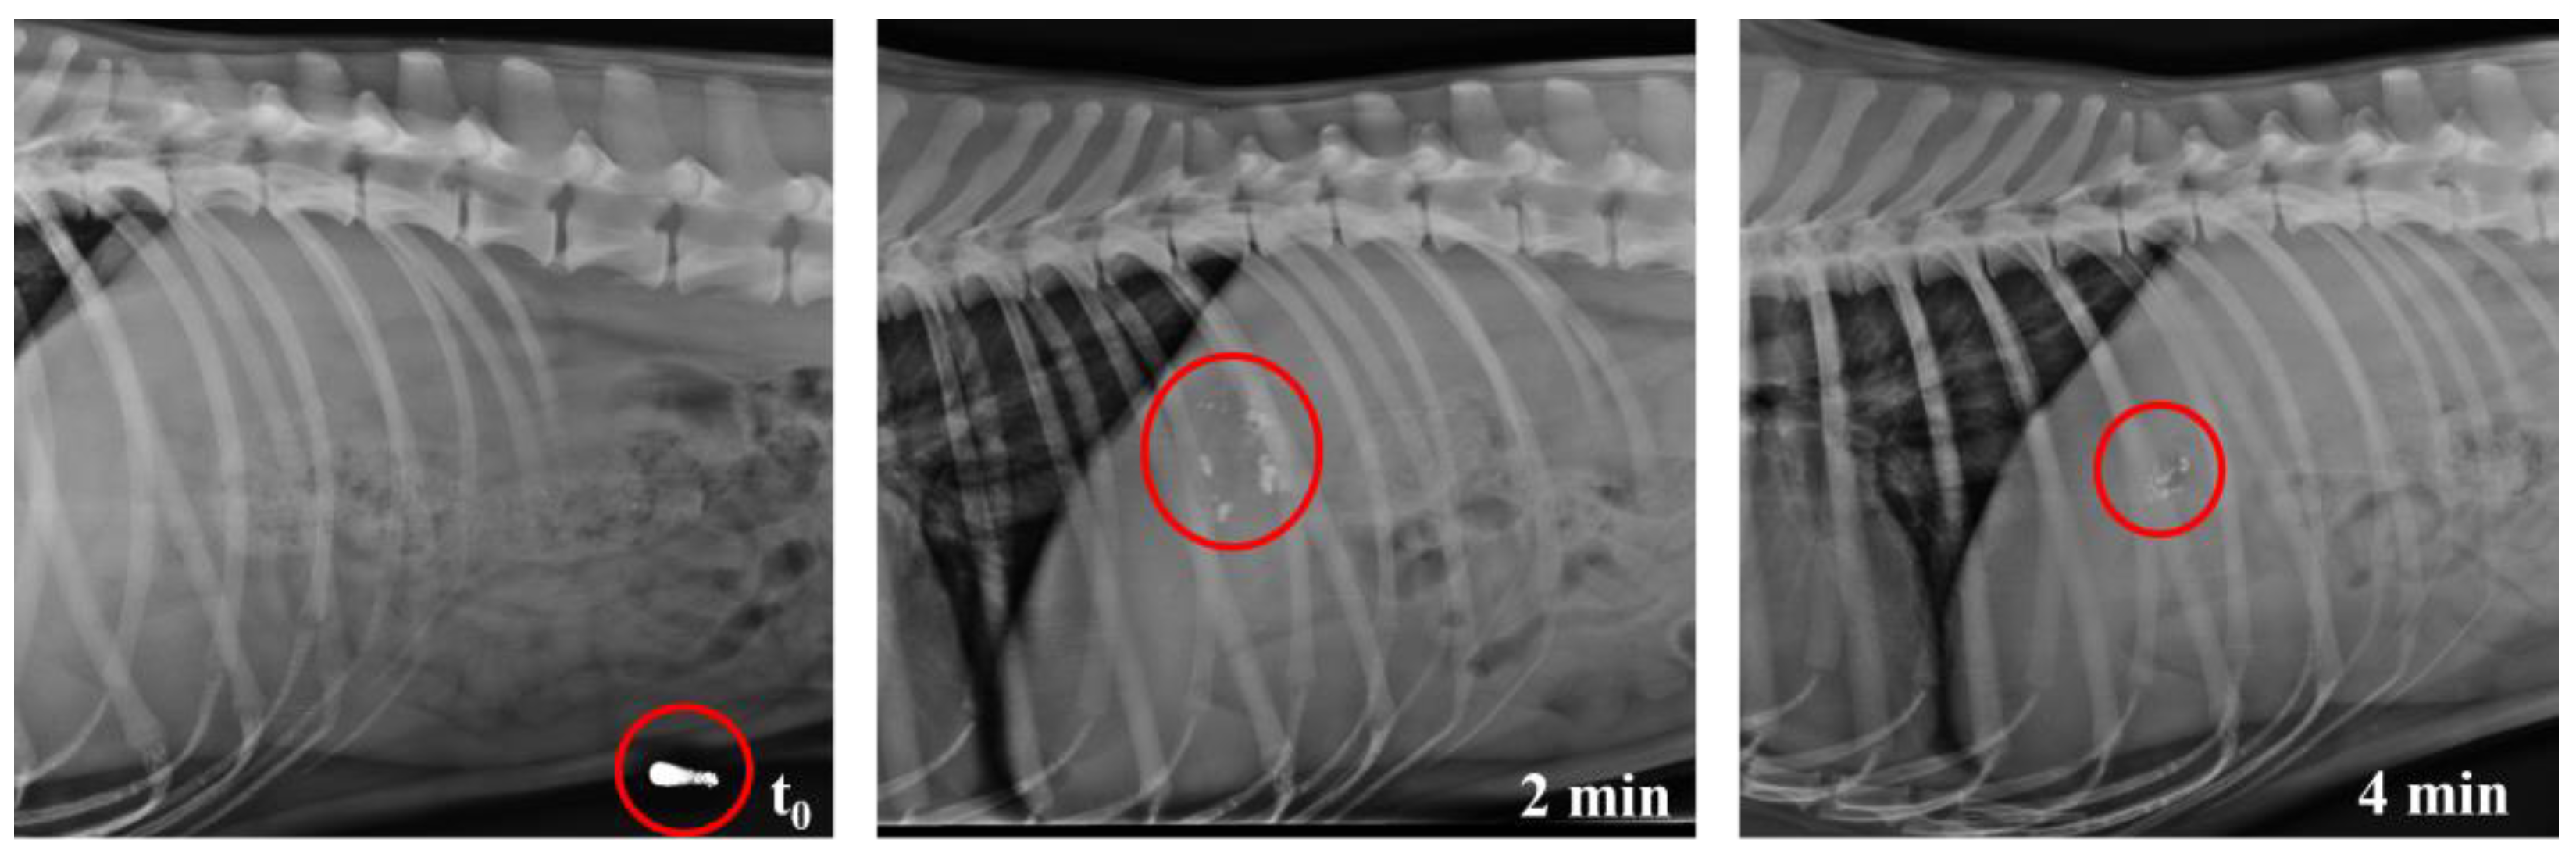

3.4. In Vivo Studies